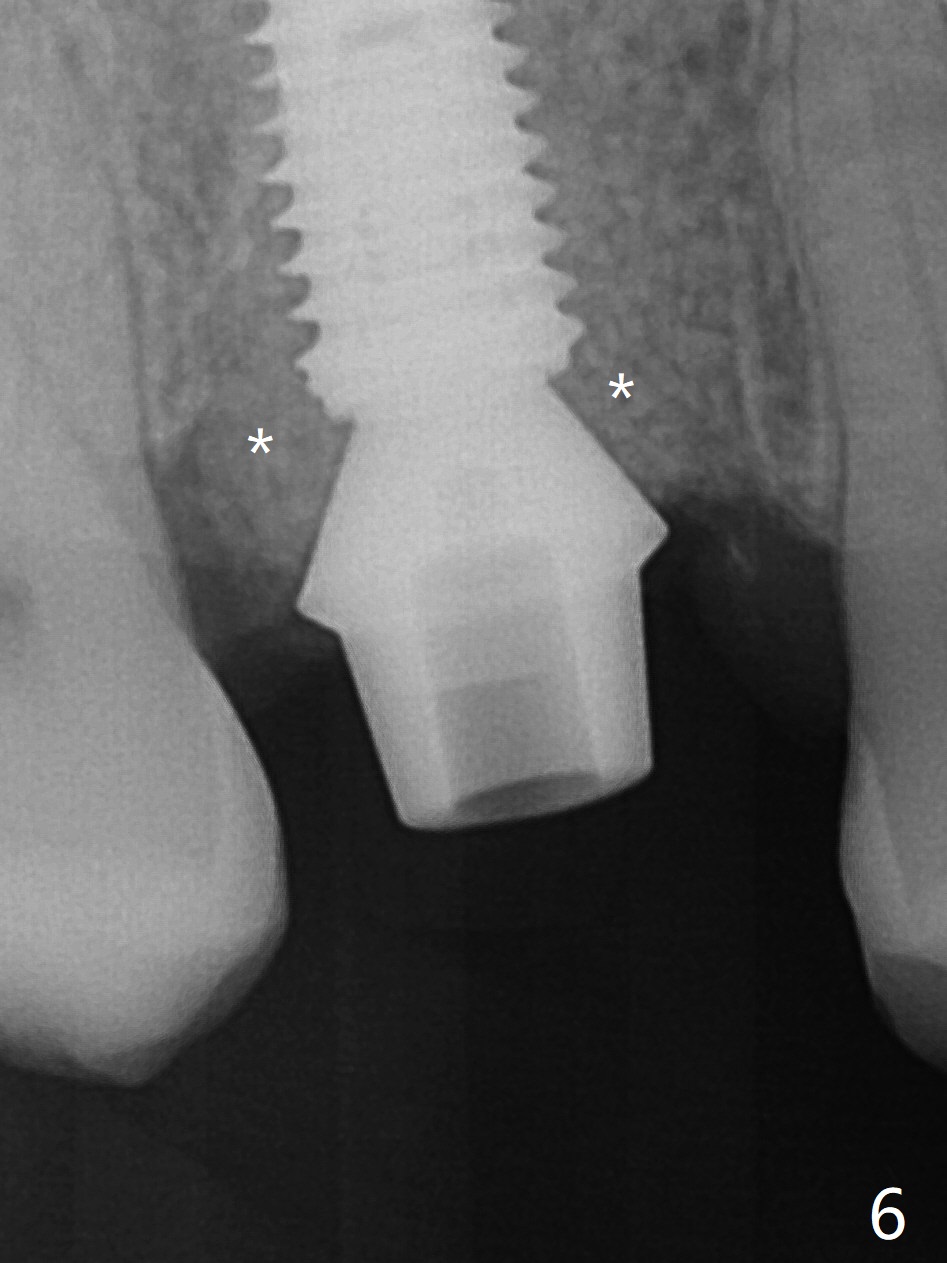

While the tooth #3 has a mesiodistal crack line, etiology may be due to chronic periodontitis with bruxism. After extraction, there is granulation tissue attached to the distobuccal (DB) root. The DB socket is larger than the mesiobuccal one (Fig.1). Osteotomy is initiated in the DB slope of the septum for 10 mm (Fig.2,3). Since there is ample apical bone, the depth of the osteotomy increases to 11.5 mm. When a 5x10 mm dummy implant is placed, primary stability is satisfactory (Fig.4 (yellow line: apical space)). The definitive implant remains the same dimension with deeper placement (Fig.5,6 (~ 20 Ncm)); with placement of a 6.5x4(3) mm abutment and Vanilla/Osteogen Graft (*), an immediate provisional is fabricated in place (without taking out for trimming) with sufficient clearance with the opposing dentition. It appears that the moderately long implant (10 mm) is able to achieve primary stability for immediate placement. When the provisional is removed 2 months postop, bone graft seems to be adhered to the socket (Fig.7). To improve local hygiene, the provisional does not return. The implant seems to have osteointegrated 3.5 months postop (Fig.8). The crown/abutment is loose approximately 1 year post cementation. Due to her daughter's contracting COVID 19, she postpones returning for approximately 1 year. The access hole is opened, crown/abutment (6.5x4(4) mm) removed, proximal contacts reduced, crown/abutment reseated without certainty. BW shows incomplete seating probably due to bony interference (Fig.9). A 5.5x4(4) mm can not be seated (bouncing, probably due to soft tissue interference). When a 4.5x5(4) mm abutment (UF) is seated, hand tightening is smooth, confirmed by BW (Fig.10). Two weeks later, the new crown is cemented intraorally. The crown/abutment is removed for cleaning. The abutment screw is torqued at 20 NCM.